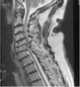

Severe spondylosis

Spondylosis is the degeneration of the vertebral column from any cause. In the more narrow sense it refers to spinal osteoarthritis, the age-related wear and tear of the spinal column, which is the most common cause of spondylosis. [Source: Wikipedia ]